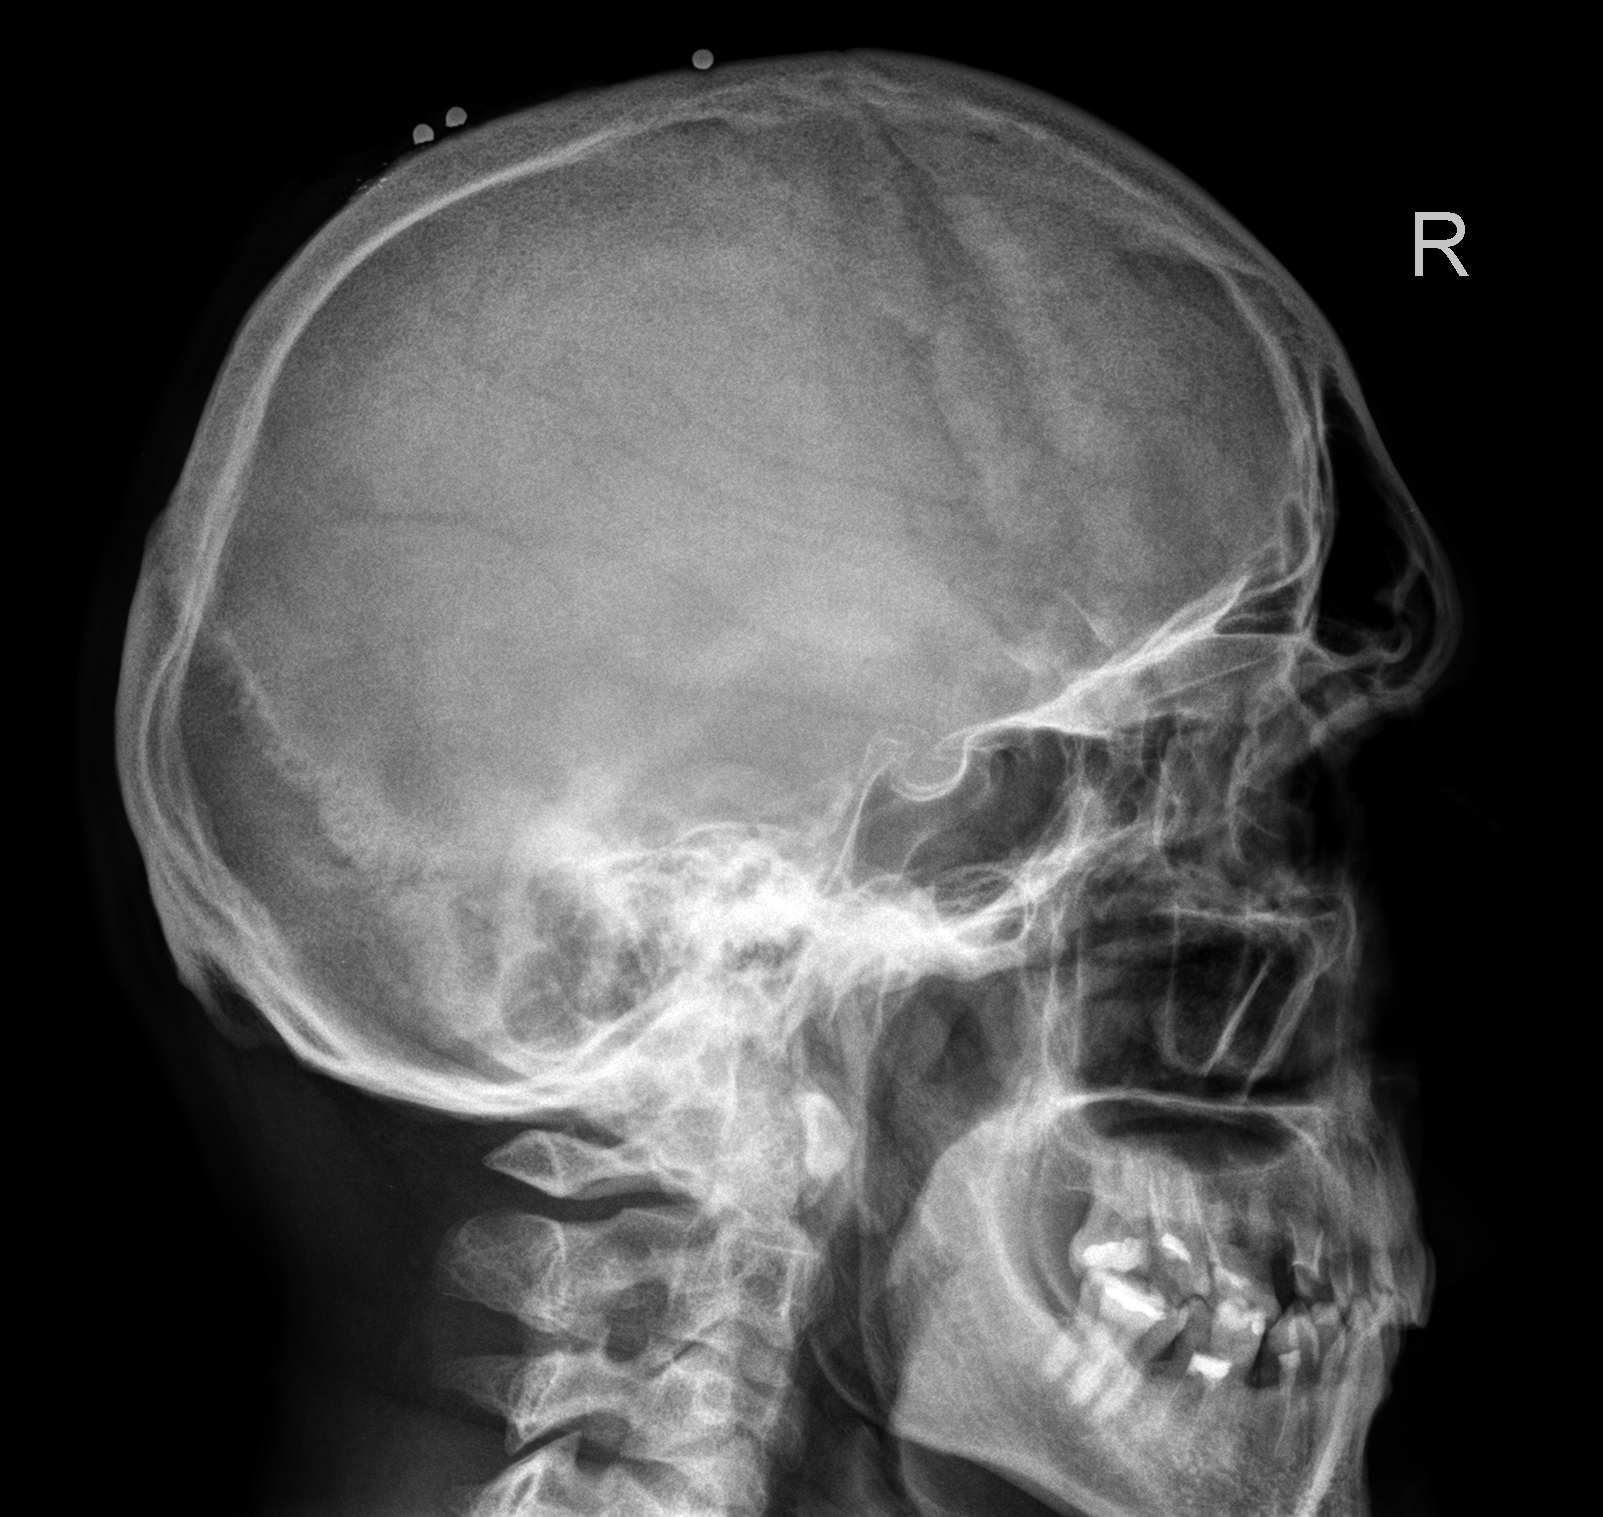

Рентгенография черепа и позвоночника: изображение и диагностика

Раздел: Необычные решения